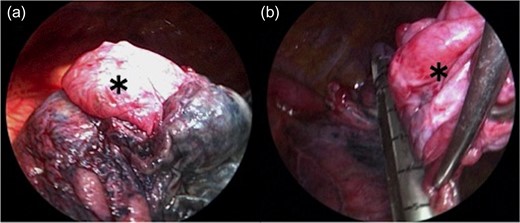

The bulla (*) wall in the apex of the lung was very thin (a). Following left lower lobectomy, the resection of emphysematous bullae (*) was performed (b).

During open thoracotomy, a large hematoma was observed extending from the chest apex to the mediastinum. The hematoma was removed, and we searched for the source of bleeding; there was no evidence of bleeding from the great vessels. Active bleeding was observed from the lung surface near the staple line, an area where the bullae had been resected. The bleeding source was cauterized and the bleeding stopped. Observation of the bleeding source revealed blood vessels growing on the visceral pleura and that the staples with tissue reinforcement were in contact (Videos 2, 3). A part of the staple in contact with the proliferating blood vessel was excised. We confirmed that there was no other bleeding site and completed the operation. The postoperative course was uneventful, and the patient was discharged on the eighth postoperative day.

In the case described above, postoperative bleeding was observed in a patient who had undergone surgical treatment that used a linear staple device with bioabsorbable PGA felt. Based on observation during the reoperation to perform hemostasis, we suspected that the bleeding was caused by the following mechanism. As the staple with the PGA sheet remained in the staple line with a certain length, the surplus staple made contact with the proliferating blood vessels on the lung surface. Thus, damage to the blood vessels occurred when the lungs expanded after the operation.